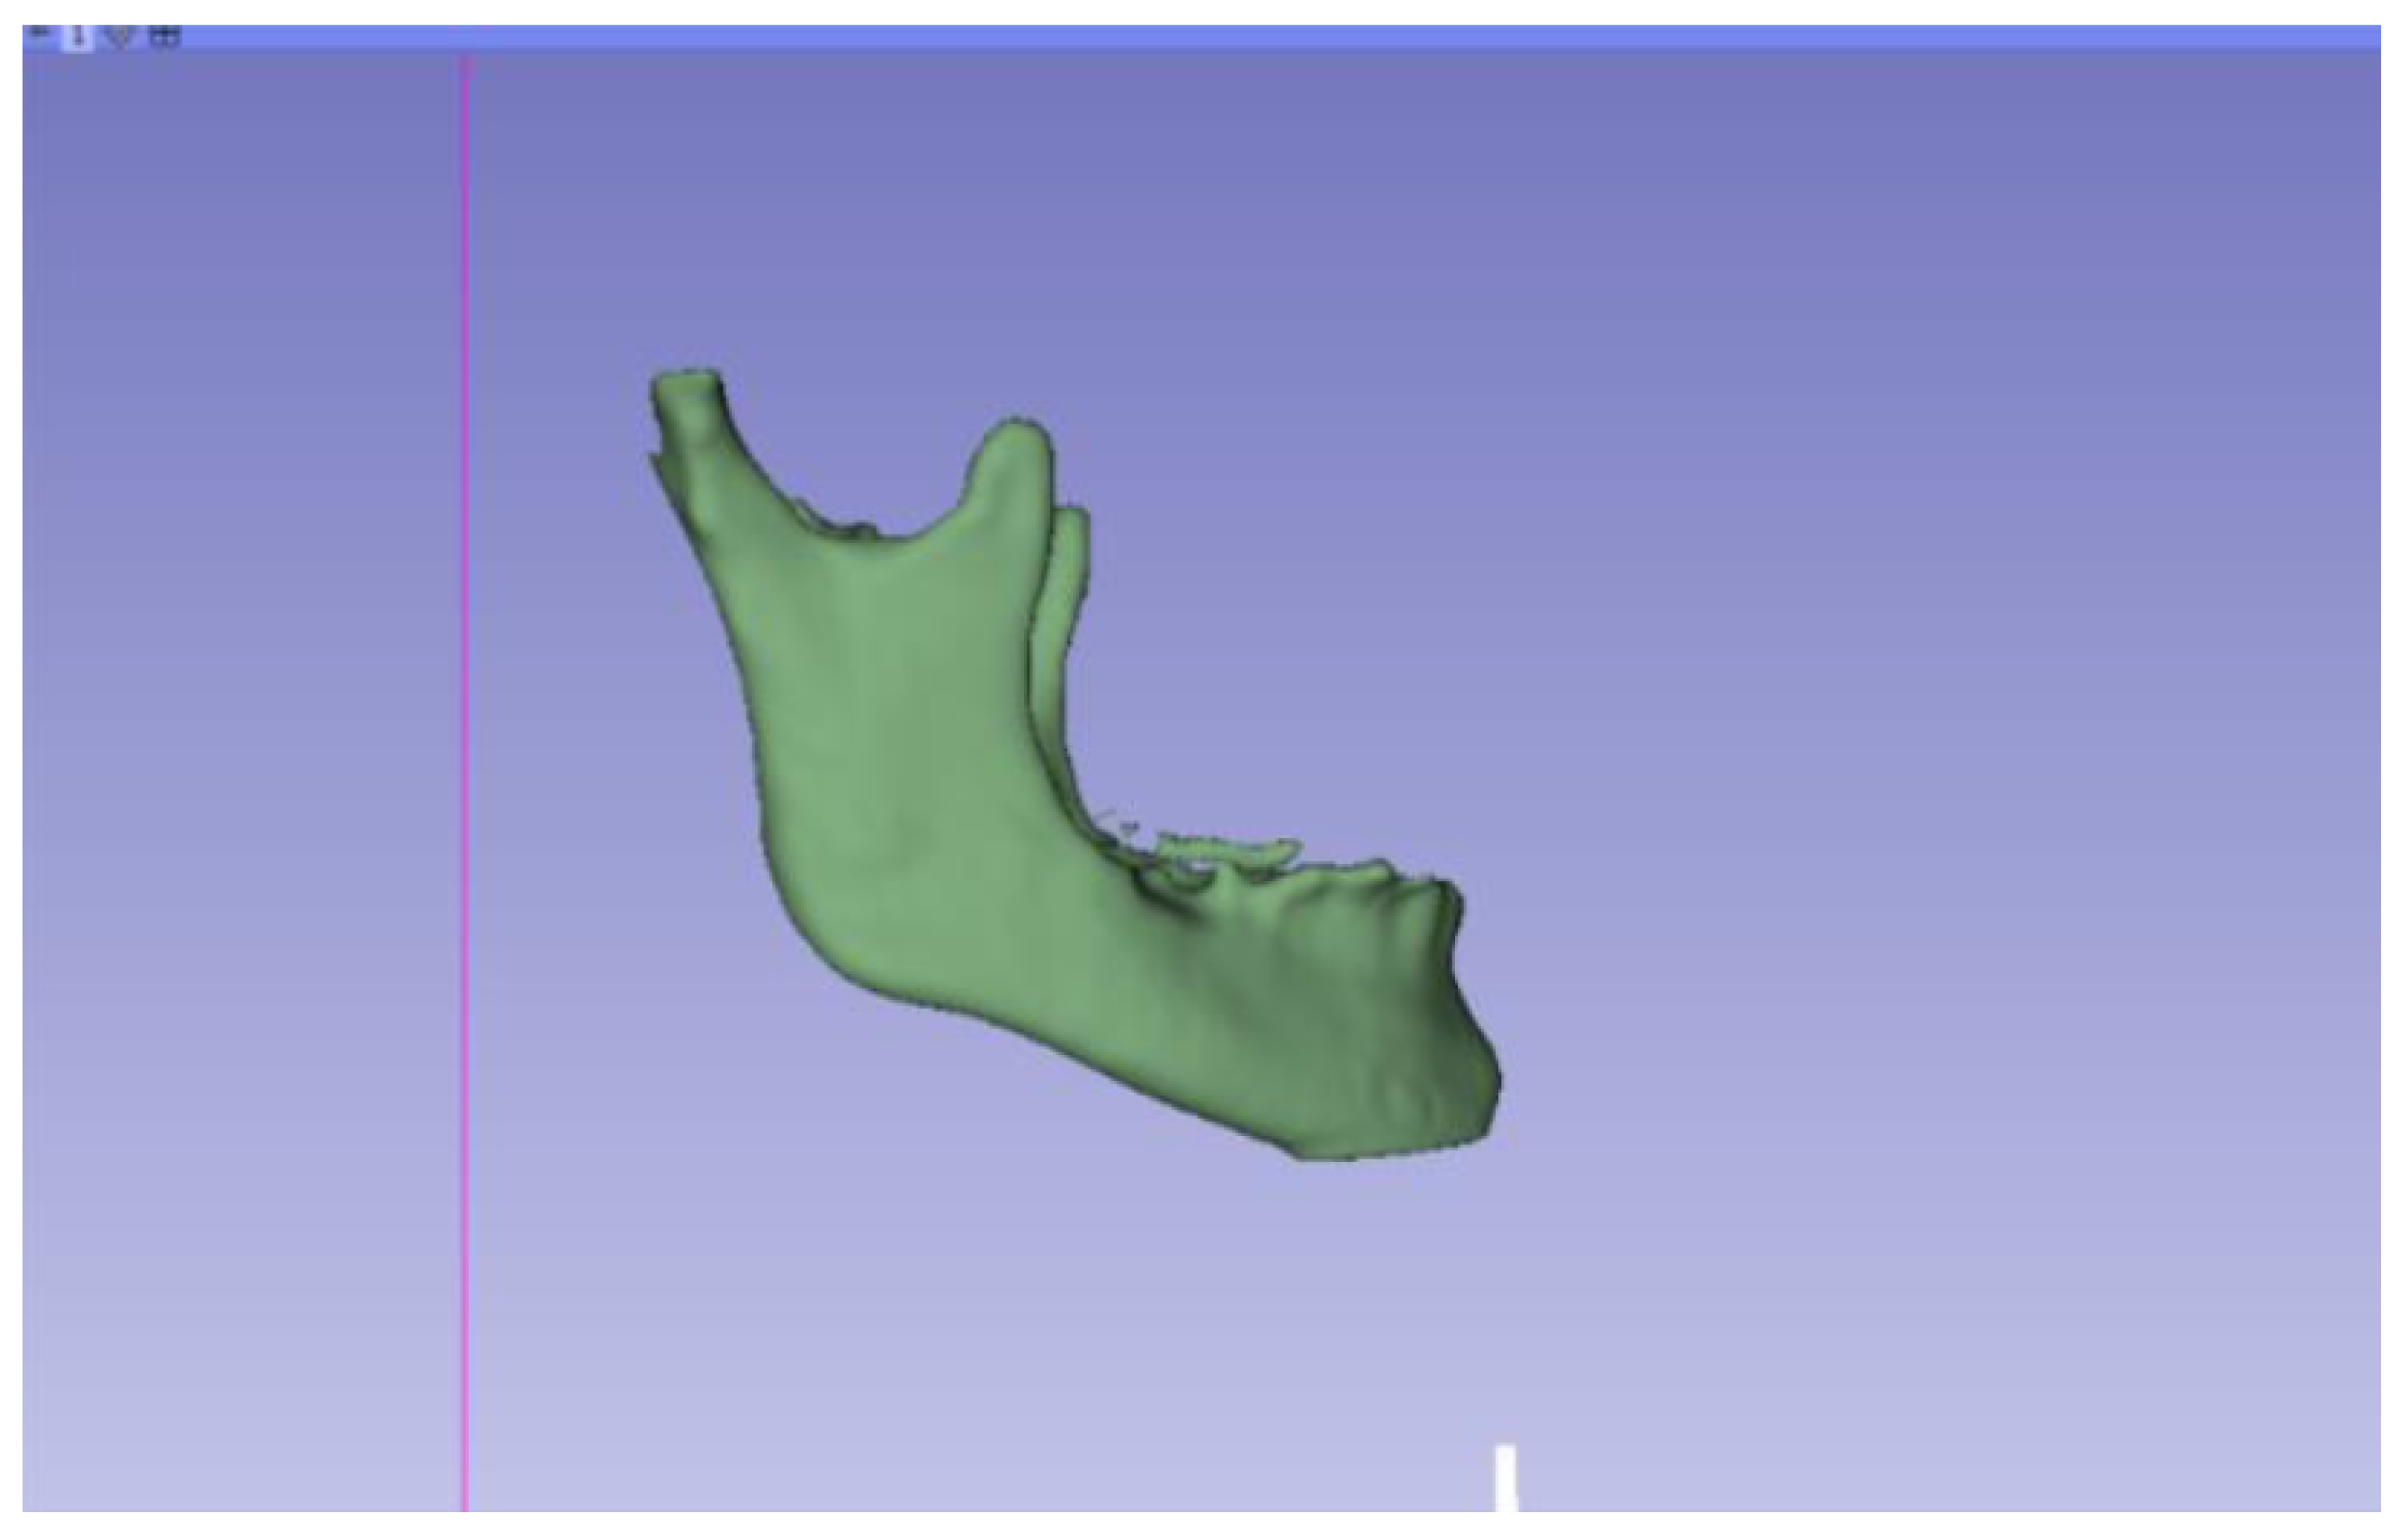

3.2. Human Lower Jaw

3.2.1. DICOM-to-STL Files